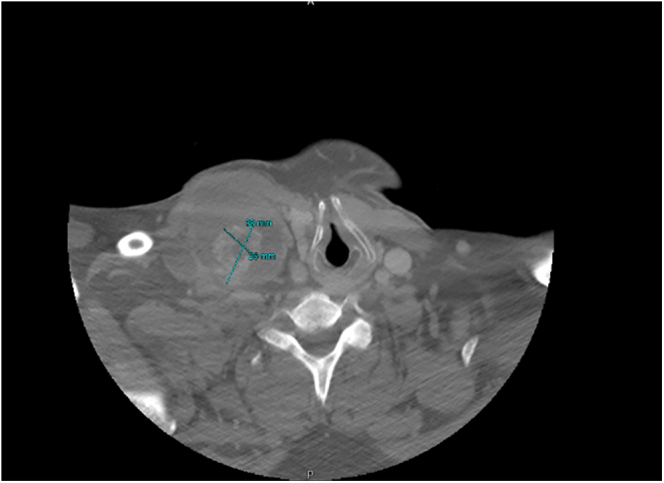

Summary: Papillary thyroid carcinoma (PTC) in a branchial cleft cyst (BCC) is exceedingly rare. This case report describes a 53-year-old male with a BCC containing PTC. Despite normal preoperative thyroid imaging, total thyroidectomy revealed multifocal bilateral micropapillary thyroid carcinoma with a contralateral metastatic lymph node, suggesting an aggressive disease course. This finding supports the likelihood that thyroid gland carcinoma metastasized to the BCC. However, the possibility of a primary tumor arising from ectopic thyroid tissue within the cyst cannot be excluded. To our knowledge, this is the 11th reported case of papillary thyroid cancer noted in a BCC. The patient underwent successful treatment, including radioiodine ablation, highlighting the importance of thorough diagnostic evaluation and management in such rare presentations.

Learning points: While most BCCs are benign, PTC can very rarely present within BCC. Metastatic PTC with a necrotic lymph node is often misdiagnosed as BCC, both radiographically and histologically. Since PTC arising as a primary tumor from ectopic thyroid tissue within a BCC is extremely rare, total thyroidectomy should be considered even in patients with radiographically normal thyroid to rule out micropapillary primary thyroid tumors. A thyroglobulin assay from the needle washout of a fine-needle aspiration of a BCC may help preoperatively identify differentiated thyroid cancers. Micropapillary thyroid cancers (<1 cm) are usually indolent, but some may show nodal metastases and clinical progression.